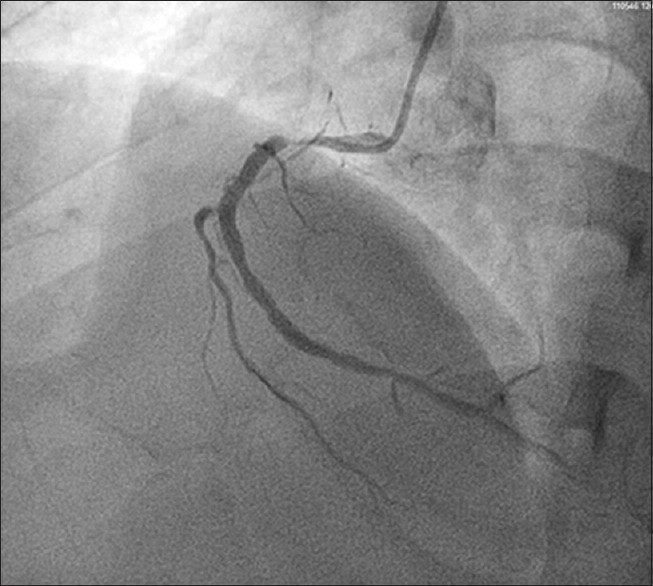

如果药物正确,使用剂量也得当,但患者依然有心绞痛存在,那么可能就是强化药物治疗后仍然无法控制的心绞痛,可能就是需要进一步冠状动脉造影检查指导下一步治疗了。如果此时还不进行冠状动脉造影等检查,可能将会出现心梗等严重并发症了。进行造影后可能需要介入或者外科搭桥的方式进行血运重建,仅仅吃药恐怕已经解决不了问题。